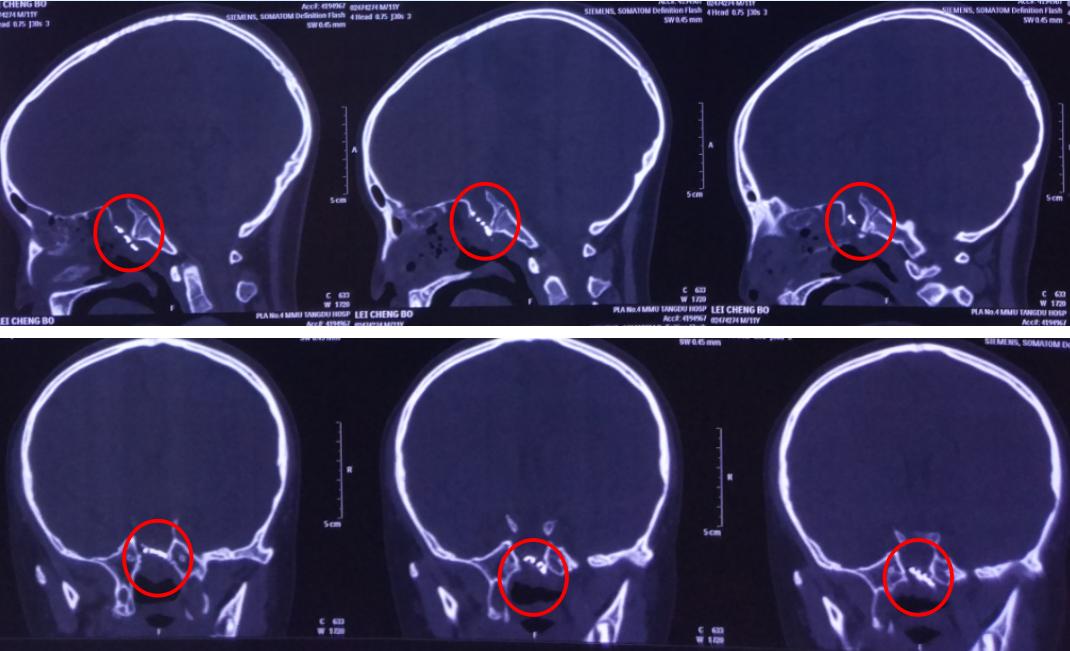

4、患者近期做头颅磁共振提示:鞍区占位性病变;

唐都医院小儿神经外科亚专业组组长王超博士结合患者病史、体征、影像学检查等诊断为先天性前颅底型颅裂,脑膜脑膨出建议及时手术。

影像资料

术后影像